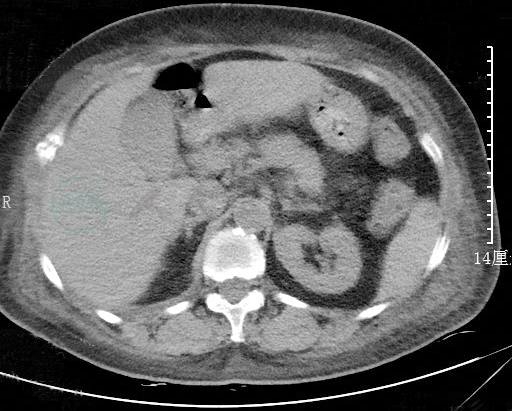

颅脑CT:颅骨多发骨质破坏并软组织影(图3)。

图3 颅脑CT

患者以腹痛、血尿淀粉酶水平升高为特点入院,初诊首先应想到急性胰腺炎,但该患者血脂肪酶不高,影像学表现缺乏典型的急性胰腺炎征象,并且临床针对急性胰腺炎的治疗未见明显效果,因此可排除急性胰腺炎的可能。入院后查体及辅助检查进一步排除了胃肠道穿孔、胆囊炎等可导致血淀粉酶轻中度升高的急腹症。同时,患者无明显腮腺区疼痛或肿胀,结合腮腺B超结果,可排除腮腺疾病导致淀粉酶水平升高。患者血清淀粉酶升高的同时,尿淀粉酶也显著增高,不符合巨淀粉酶血症的特点。另外,患者肾功能正常,排除了因肾小球滤过率下降而导致的高淀粉酶血症。综合以上资料,考虑该病例为肿瘤细胞合成分泌淀粉酶所致的高淀粉酶血症。患者腹部CT提示多发骨质破坏,但未见明显实体肿瘤,结合血IgG及血、尿λ轻链升高,头颅CT、骨盆X线片多部位骨质破坏,高度提示多发性骨髓瘤可能,随后的骨髓穿刺活检结果确诊了多发性骨髓瘤。